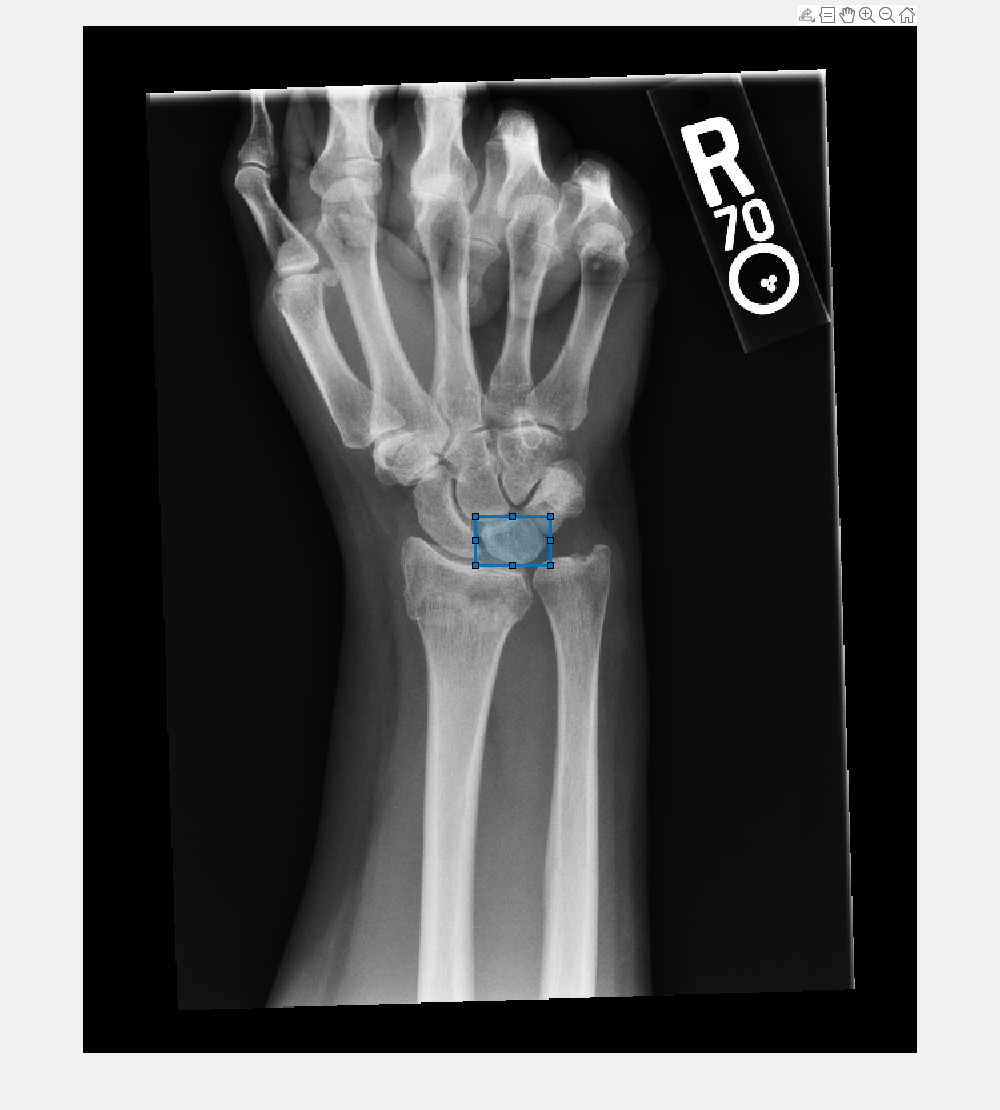

The Medical Segment Anything Model (MedSAM) is a Segment Anything Model (SAM)

fine-tuned for medical image segmentation on a large-scale medical image data set. Use the

medicalSegmentAnythingModel object and its object functions to

interactively segment objects in 2-D medical images using visual prompts. A

medicalSegmentAnythingModel object configures MedSAM for semantic

segmentation of objects in a medical image without retraining the model. To segment an image,

you must first use the extractEmbeddings object function to extract the image embeddings from the

MedSAM image encoder. Then, use the segmentObjectsFromEmbeddings object function to segment objects from the image

embeddings using the mask decoder.